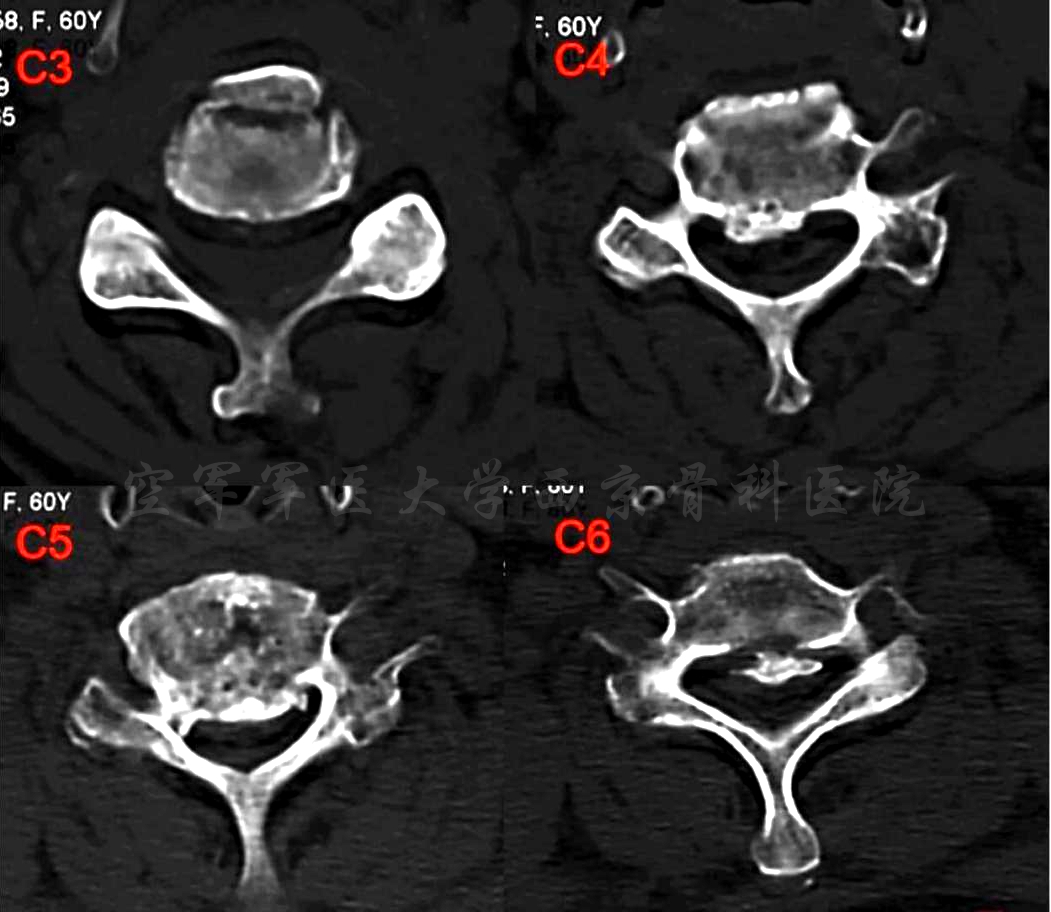

术前MRI